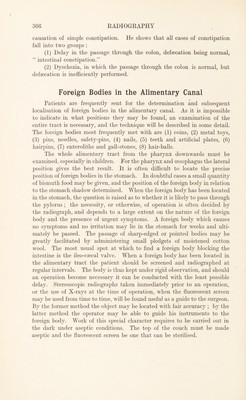

Radiography and radio-therapeutics / by Robert Knox.

- Knox, Robert, 1868-1928